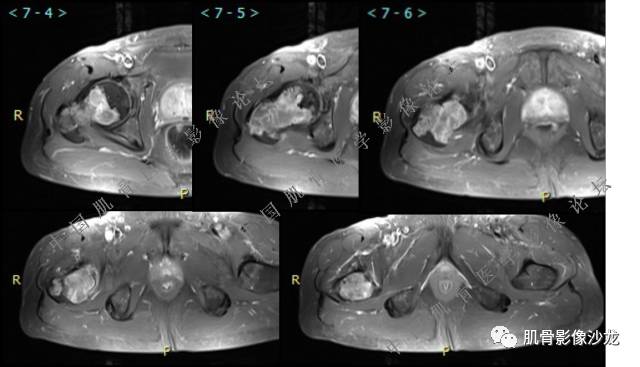

主诉:右大腿疼痛、活动受限20天

现病史:患者于20天前无明显诱因出现右下肢疼痛,活动受限,疼痛呈阵发性,活动后加重。自行口服止痛药芬必得,效果不佳,至当地医院治疗,检查发现右侧股骨近端病变。遂来诊

葛英霖 20:30 原发或继发动脉瘤样骨囊肿,继发于巨细胞瘤,软骨母,纤维组织细胞瘤,骨母等等

向以四 20:30 软骨母合并ABC,

医影在线 20:30 软骨母,/继发ABC

飞鹰行动 20:31 T2信号高,有软骨成分

Echo 20:32 T2确实有一块区域很亮 ,并有野液平

飞鹰行动 20:33 有侵袭性

飞鹰行动 20:35 骨皮质破坏,周围骨质异常信号

葛英霖 20:36 这不是良性病变

葛英霖 20:36 中间型可能性极大

葛英霖 20:37 明显侵蚀骨内膜啊,硬化边也不完整 (细箭头所示)

葛英霖 20:43 提不提也很明显继发了abc

Echo 20:44 葛老师~继发ABC是根据有液液平面判断么?

葛英霖 20:44 是

葛英霖 20:45 abc就是出血来的

葛英霖 20:46 明显的多囊状改变,液液平面